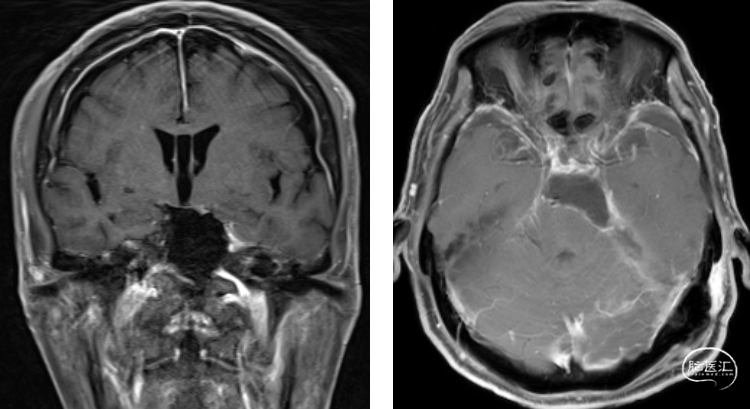

06

术后影像

![]()